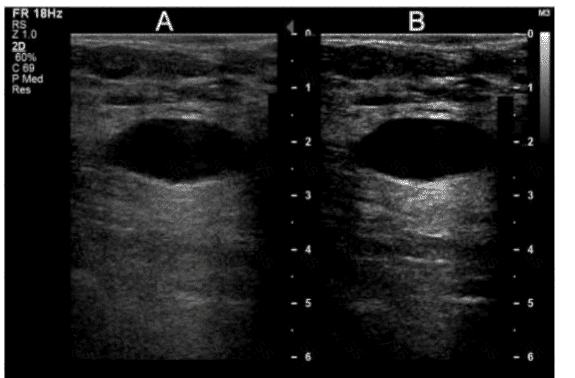

The calipers in this image measure which performance characteristic of a system?

A.

Depth measurement accuracy

B.

Dynamic range

C.

Axial resolution

D.

Lateral resolution